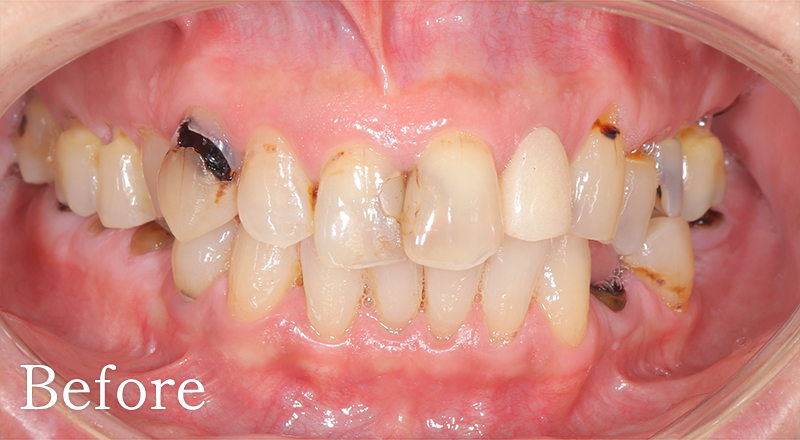

CASE4

骨格1級患者に対し、臼歯部にインプラント治療を行い咬合回復を行なった1症例

主訴 右側でうまく噛めない

治療内容 下顎臼歯部インプラント、咬合再構成、上顎矯正治療、セラミック治療

治療期間 約2年

費用 診断料:22万円(税込)

下顎顎臼歯部インプラント埋入手術:22万円(税込)×4本

セラミック補綴:22万円(税込)×4本

セラミック治療:11万円(税込)×9本

矯正治療:44万円(税込)